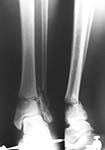

Middle aged adult was injured while travelling in a train(accidentally put his leg out). Presented with injury to left lower leg. Lacerated wound over the fibular fracture. Also another wound over the foot anterolaterally. No deficits.

On day one wound debridement followed by calcaneal traction done. Needs further stabilisation and a small split graft laterally. At present the fragments are putting pressure on the anterior skin. Will be happy to get your opinion on possible methods of stabilisation.

Day 1

Traction